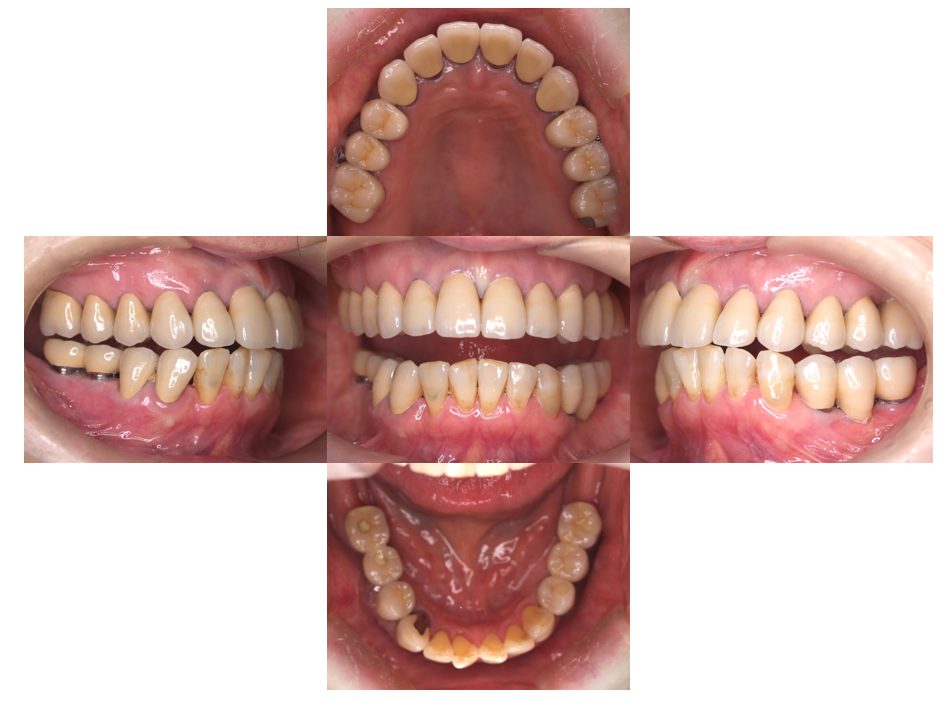

矯正治療・インプラント治療・セラミック治療の症例紹介(三隅歯科クリニック)

三隅 賢祐(三隅歯科クリニック)

症例詳細

| 主訴 | 30代女性 顎関節が痛い。見た目も気になる |

| 治療内容 | 矯正治療を行いました。 |

| 治療費 | 1,700,000円(税込み) |

| 治療期間 | 3年(矯正治療期間 2年半) |

| 治療回数 | 40回 |

| 想定されたリスク | 術前に精密な診査診断とシミュレーションを行い、インプラントを適正なポジションに埋入しておかないと、インプラント自体が矯正治療の邪魔になるリスクがあった。 |